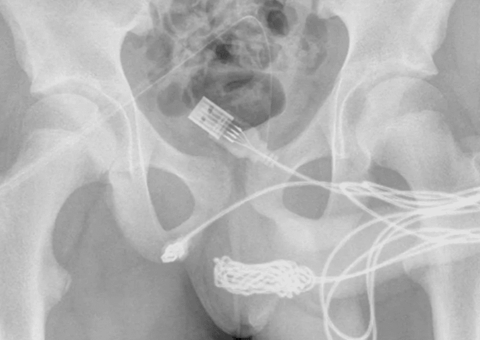

Um sapo foi arremessado para dentro de um presídio de Monte Carlos, em Minas Gerais. Agentes penitenciários encontraram o animal morto e dentro dele um celular.

Os agentes ouviram um barulho e foram verificar. Ao chegarem, encontraram o anfíbio em cima de um telhado de uma marcenaria. Ao tocarem o animal, perceberam que dentro dele havia um celular.